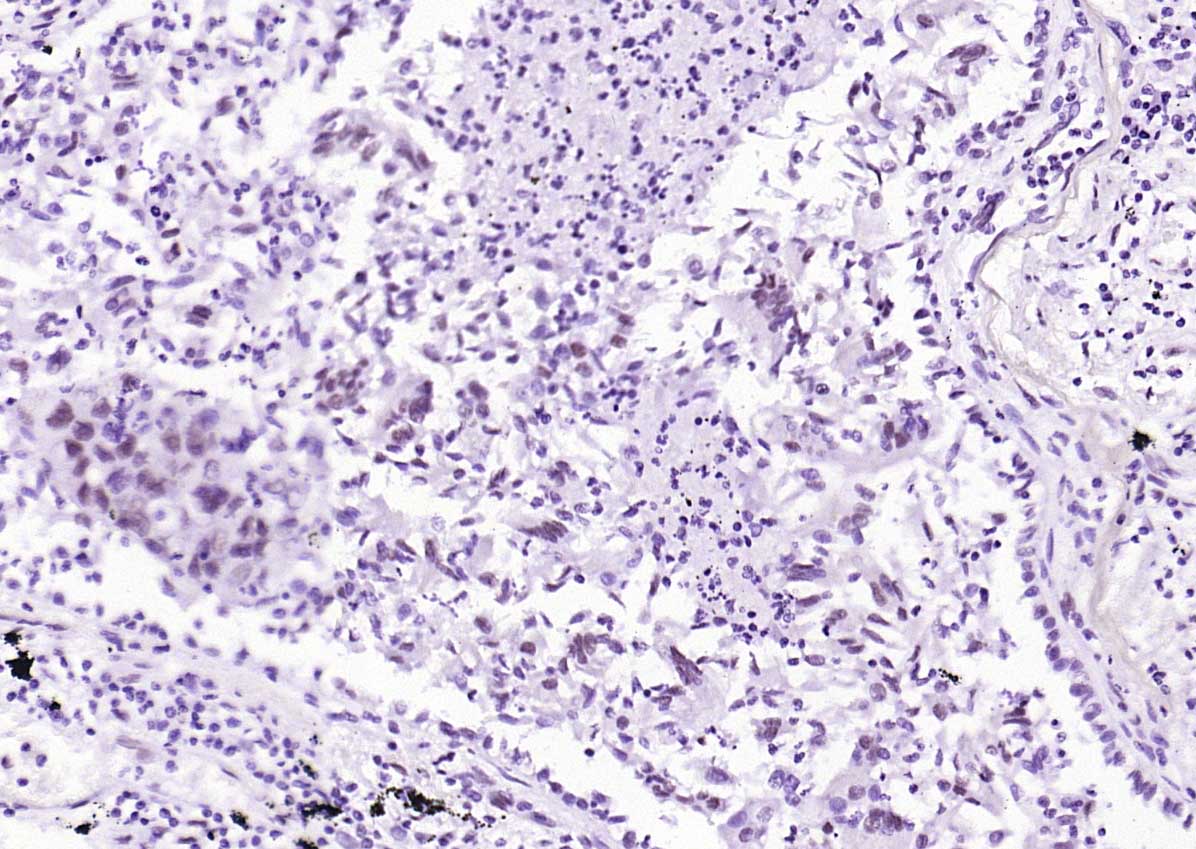

| 产品应用 | WB=1:500-1000, IHC-P=1:50-200, IHC-F=1:50-200, IF=1:50-200 Not yet tested in other applications. |

| {IHC-P} | {1:50-200} |

| {IHC-F} | {1:50-200} |